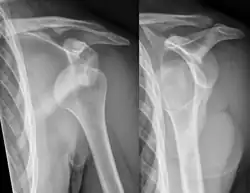

A shoulder dislocation often occurs as a result of a fall onto an outstretched arm or onto the shoulder.[3] Diagnosis is typically based on symptoms and confirmed by X-rays.[2] They are classified as anterior, posterior, inferior, and superior with most being anterior.[2][1]

A diagnosis of shoulder dislocation is often suspected based on the person's history and physical examination. Radiographs are made to confirm the diagnosis. Most dislocations are apparent on radiographs showing incongruence of the glenohumeral joint. Posterior dislocations may be hard to detect on standard AP radiographs, but are more readily detected on other views. After reduction, radiographs are usually repeated to confirm successful reduction and to detect bone damage. After repeated shoulder dislocations, an MRI scan may be used to assess soft tissue damage. In regards to recurrent dislocations, the apprehension test (anterior instability) and sulcus sign (inferior instability) are useful methods for determining predisposition to future dislocation.

Anterior dislocation of the right shoulder. AP X ray -

Anterior dislocation of the right shoulder. Y view X ray.